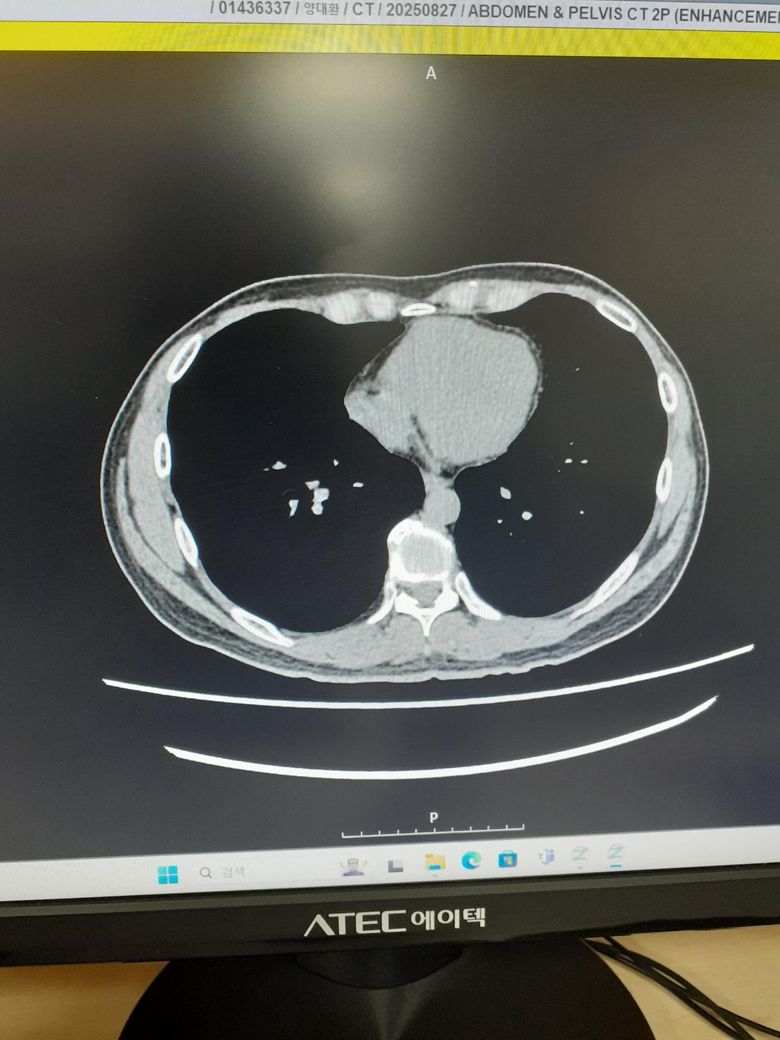

ct사진좀봐주세요사례합니다 조영제십니다

이상 없다고집으로보냅니다 전립선난종과만성담낭염같은데이상 없다내요왜그러죠

소변통 성관계통증도잇는데최근에복부통증이심해졋어요